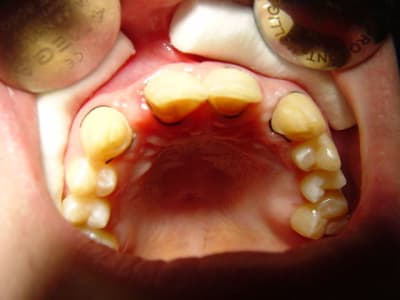

bonjour, le cas :

Dsc00091 vo4p11 - Eugenol

ceci par exemple

Dsc00090 mq4djg - Eugenol

26/11/2010 à 22h47

préparations pour bridge collé ...des commentaires?